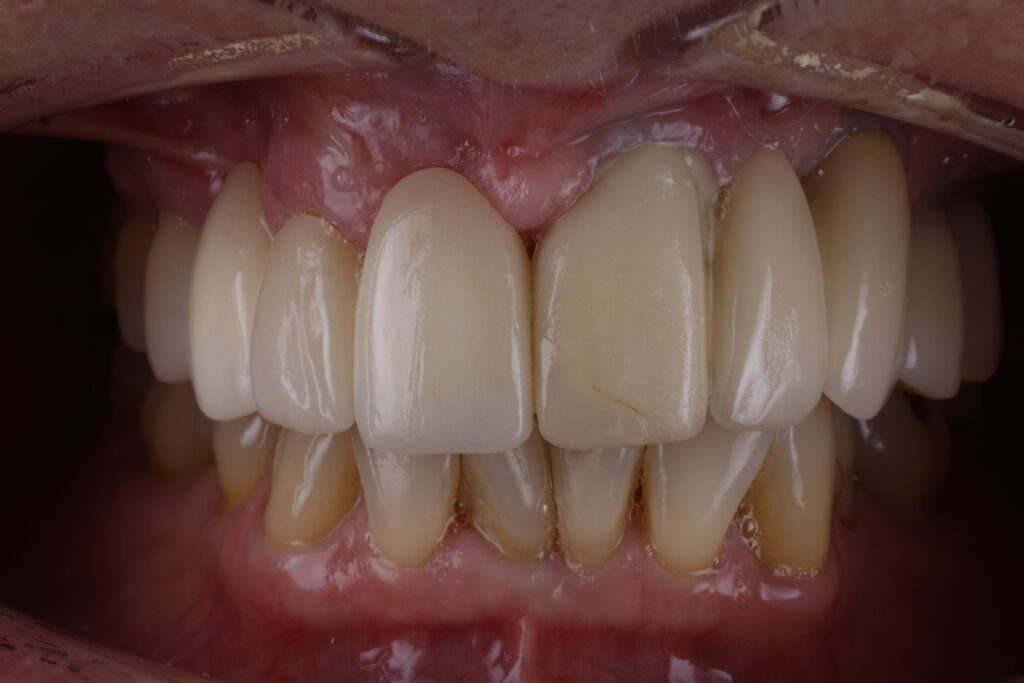

Before

After